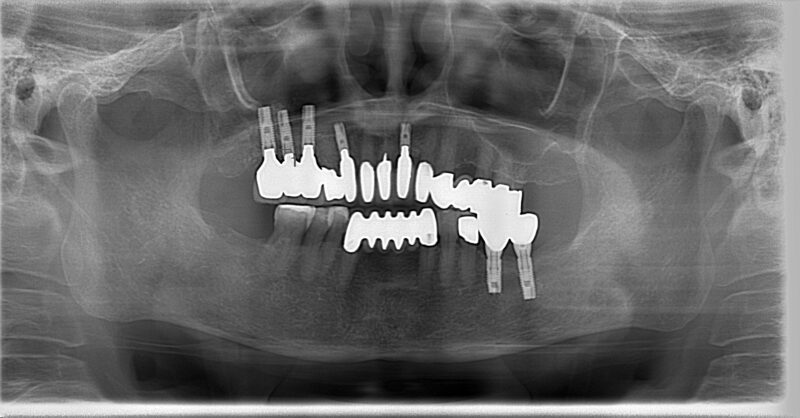

■ 20年経った今(2025年)

あれから20年。

インプラントはすべてしっかりと機能しています。

歯ぐきも健康で、噛み合わせも安定しています。

まるで自分の歯のように使えているのです。

20年経っても、歯の見た目はほとんど変わりません。

右下の素材をより強いセラミックに変えたくらいで、

全体の印象はほぼ当時のまま。